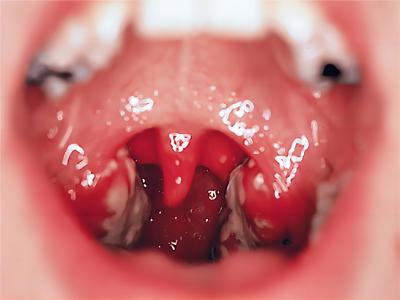

扁桃体

红肿 · 充血

急性隐窝性扁桃体炎扁桃体又红又肿图

急性隐窝性扁桃体炎患者的咽部黏膜呈弥漫性充血,两侧扁桃体及两腭弓发红、肿胀,局部存在一个黄白色点状渗出物,伴有咽痛、吞咽困难等不适症状。